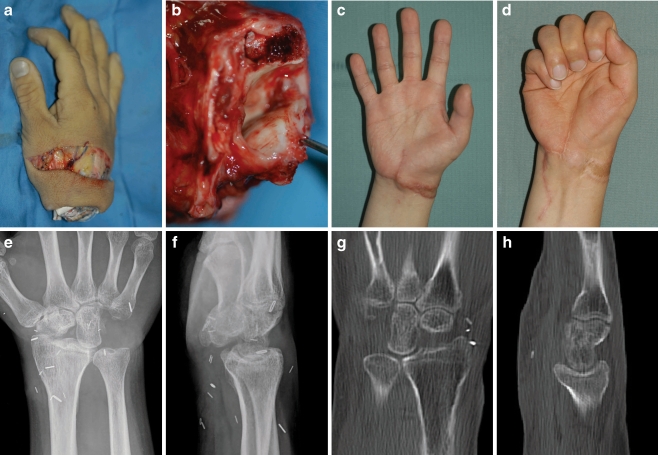

After a follow-up period of 21 months, postoperative evaluation revealed that a “good” result was achieved as per Chen’s criteria. Muscle strength was M4. The key-pinch was 13 lbs, and the grip power was 40 lbs, which was 48% and 45% of the intact contralateral side, respectively. The static two-point discrimination of the fingers averaged 10 to 12 mm. Active range of motion of the wrist was 45°, with 20° of flexion and 25° of extension. Total active range of motion of all fingers averaged 225° and that of the thumb was 160°. On the final follow-up, the patient did not complain of any pain. On the MRI, CT, and plain X-ray, there was no evidence of degenerative changes on the articular surface of both the head of capitate and lunate facet of the radius. Minimal displacement of capitate toward ulnar side was noted (Fig. 1).

Figure 1.

a–d Preoperative view of a guillotine-type amputation of the wrist at the radio-carpal joint. e, f Postoperatively, radiograph shows wrist joint fixation using 3-Kirschner’s wires after proximal row carpectomy. g–j Appearance of the replanted wrist 21 months postoperatively. k & l, MRI demonstrates intact radio-capitate joint without any arthritic changes and perseverance of 1 mm width.